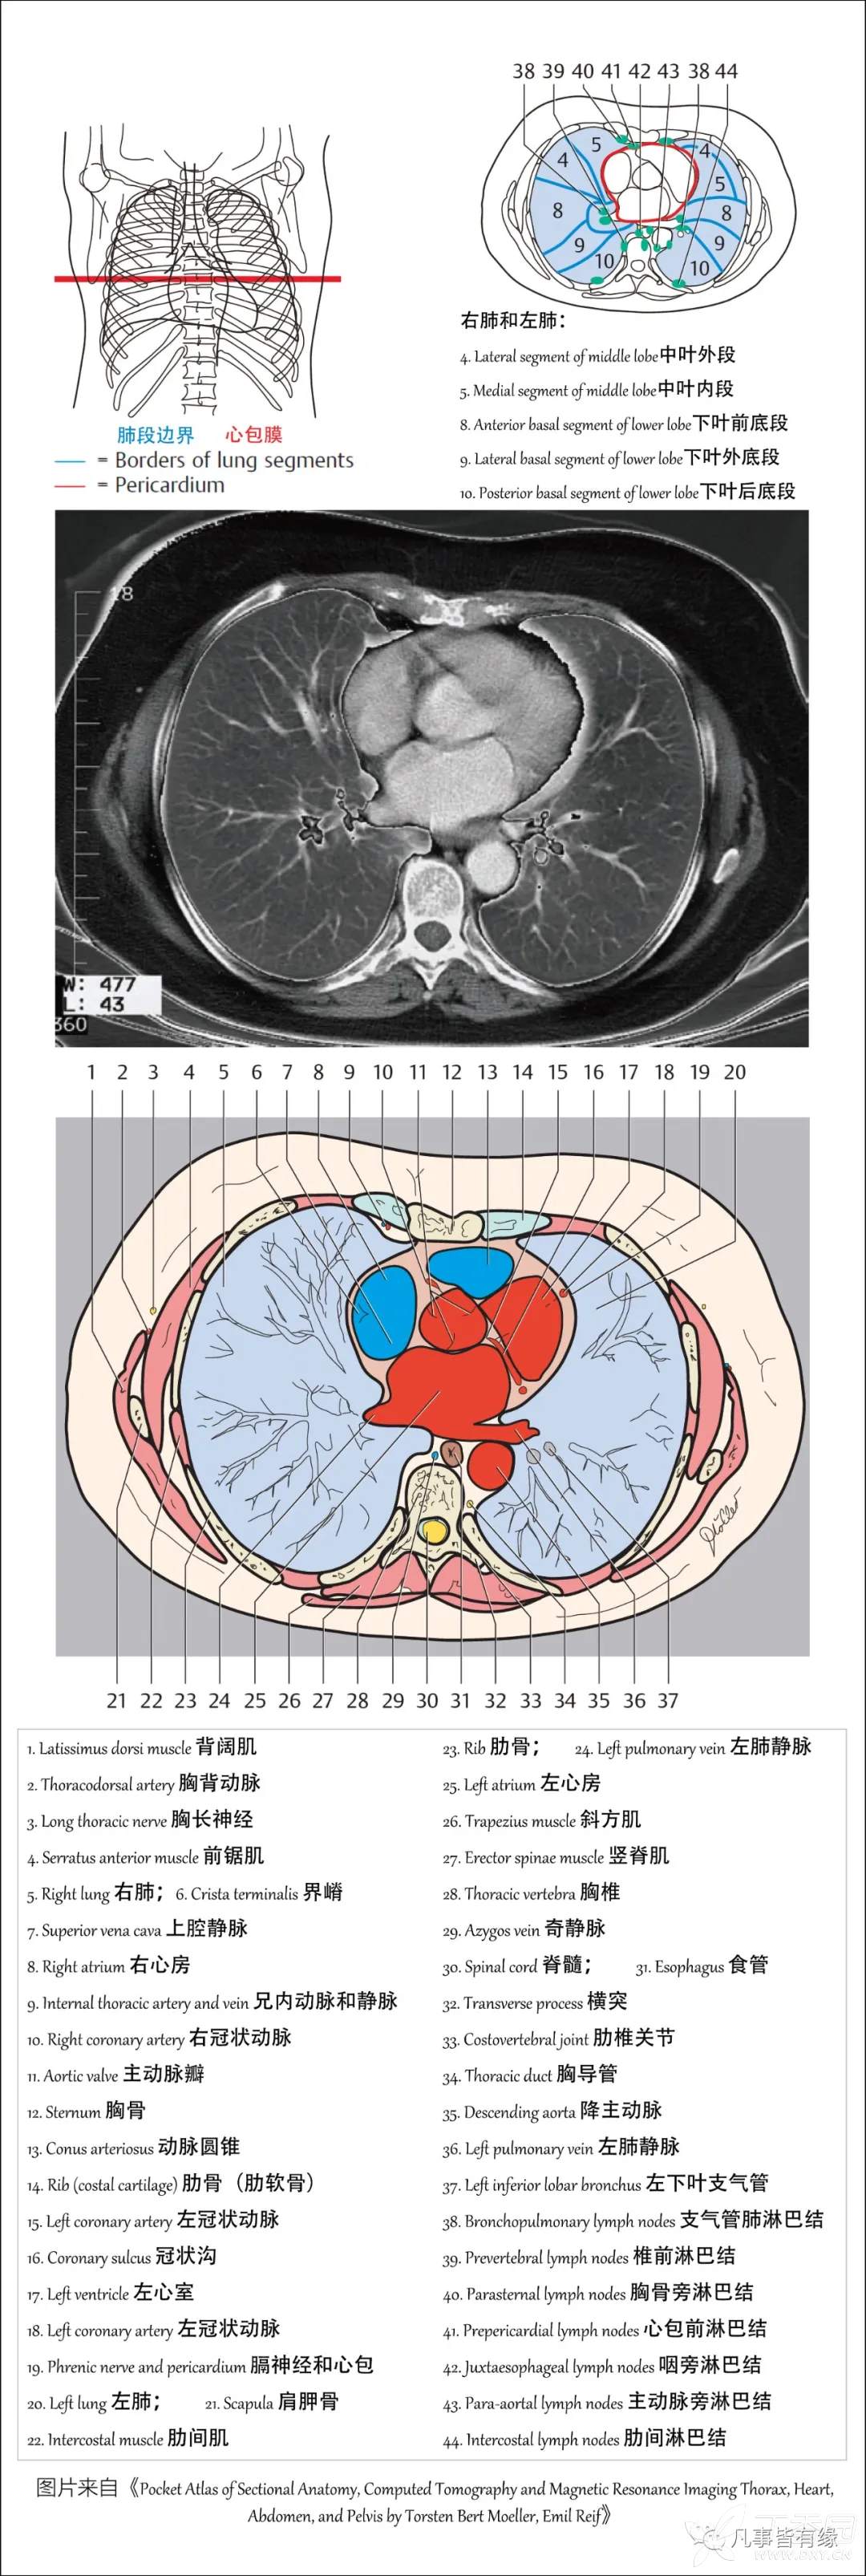

(一)胸部CT轴位断层解剖: